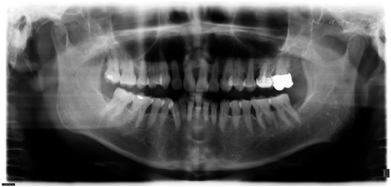

全口临床检查:口腔卫生状况一般,菌斑、软垢少量,下前牙舌侧可见新生牙石,龈下牙石(++)。牙龈色偏红,肿胀,形态圆钝,质软,尤以下前牙舌侧为重,出血指数3~4。全口牙齿探诊深度(PD)5~7 mm,个别位点8~9 mm。全口牙齿均可探及附着丧失,21、24、25、41、43松动I~Ⅱ。46合面金属色充填体,27烤瓷冠复体,近中悬突,可见食物嵌塞,叩痛(-)。咬合关系深覆合,下前牙多生牙,下前牙区拥挤,43位置颊倾,反合,见图1,图2,图3。

全口影像学检查:12~22、25~26、34~36、45~46牙槽骨吸收进一步加重,但下颌出现骨白线,26远中冠部低密度影像近髓腔,根尖周无低密度影像。